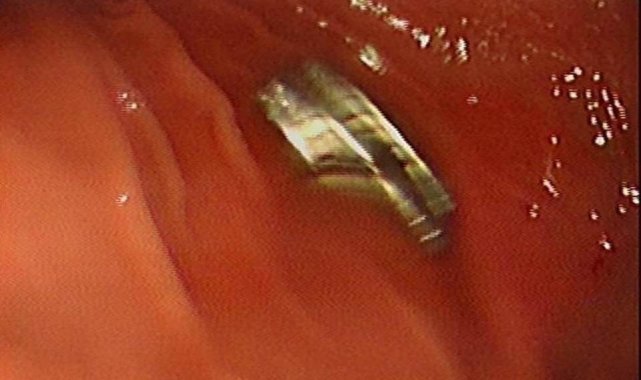

Edinilen bilgiye göre, Erzurum'da bir çocuk evde bulunan 19 tane mıknatısı yuttu. Çocuğun rahatsızlanması sonucu durumu öğrenen aile hastaneye başvurdu. Daha sonra çocuk Elazığ'a sevk edildi. Fırat Üniversitesi Çocuk Gastroenteroloji Hepatoloji ve Beslenme Bilim Dalı Başkanı Prof. Dr. Yaşar Doğan, çocuk hastanın yemek borusuna yapışmış 19 mıknatısı endoskopik yöntemle çıkardı.

Mıknatıslar uzun süre yemek borusunda takılı kaldığı için yemek borusu ve mide girişinde zedelenmeler olurken, çocuğun sağlık durumunun iyi olduğu ve taburcu edildiği öğrenildi.